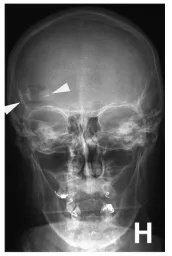

▼(H)术后x线片显示开颅面积(箭头)和骨瓣2颅钉固定(B)。Braun Melsungen AG,德国Melsungen)夹具。